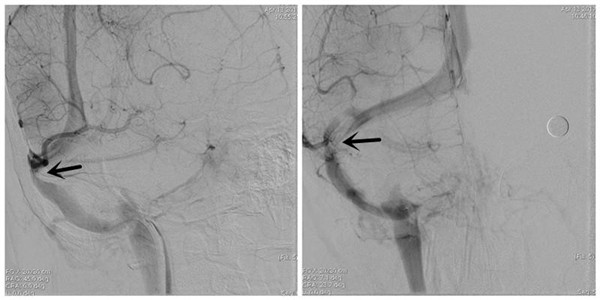

术前DSA示:右侧横窦狭窄(箭头所示)